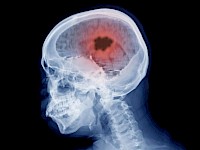

研究新突破:對最致命的腦癌可進行更好的治療

研究成人中最常見和最具侵襲性的腦腫瘤類型的科學(xué)家發(fā)現(xiàn)了一種分析同一患者患病和健康細胞的新方法。